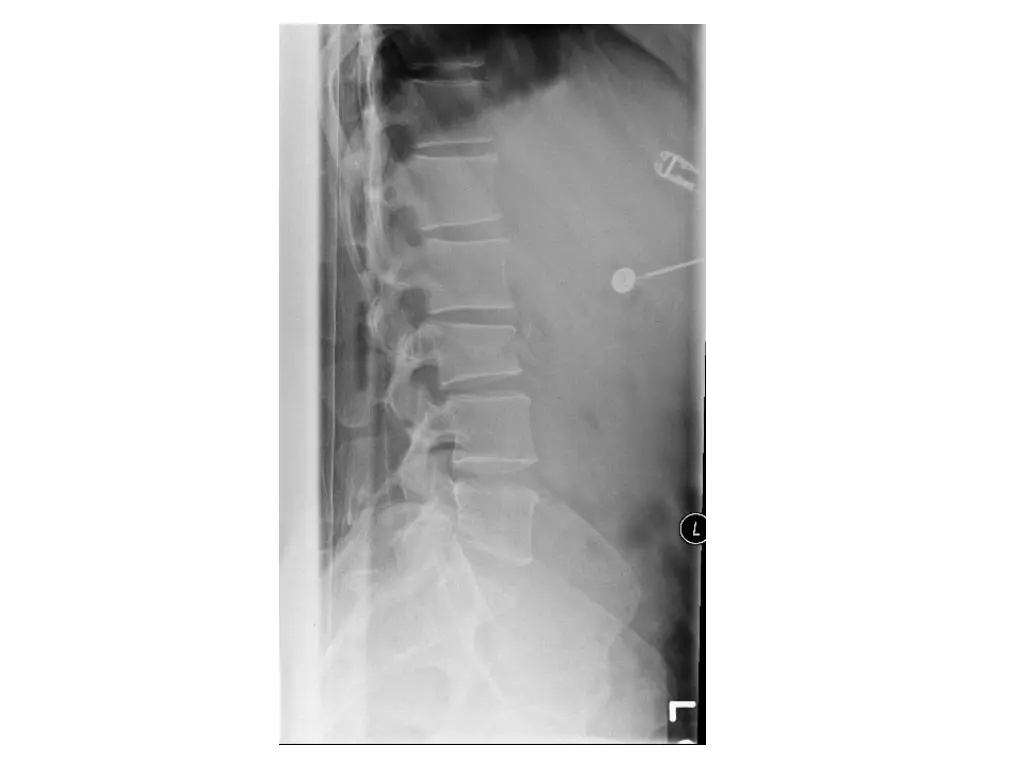

Imaging (Case 2) Lateral XR Midsagittal CT scan Parasagittal CT scan Axial CT scan

Imaging (Case 3) Lateral XR Midsagittal CT scan Parasagittal CT scan